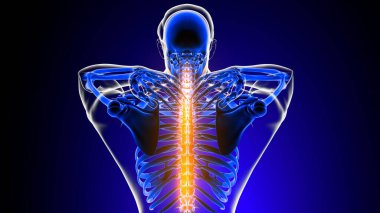

İnsan iskeleti anatomisi Scapula Kemiği Tıbbi Konsept için 3D Hazırlama

İskeletanatomiçene kemiğiyarım ayboyunlomberetmoidcapitateAltkısmınıHamate3d oluşturmaGöğüs kafesi3B illüstrasyoncarpalsağız sapımetakarplaralın kemiğiApendiküleruyluk kemiğioksipital kemikBurun kemiğikemiğigöğüs kemiğinin gövdesiayak kemikleriyarıçap kemiğiparietal kemikeksenel iskeletKalça kemiğilacrimal bonepalatine boneproximal phalangesinferior nasal conchaintermediate phalangesdistal phalangesclavicle bonekaval kemiğiBurun kıkırdağıkol kemiğikürek kemiğiBenzer İçerikler